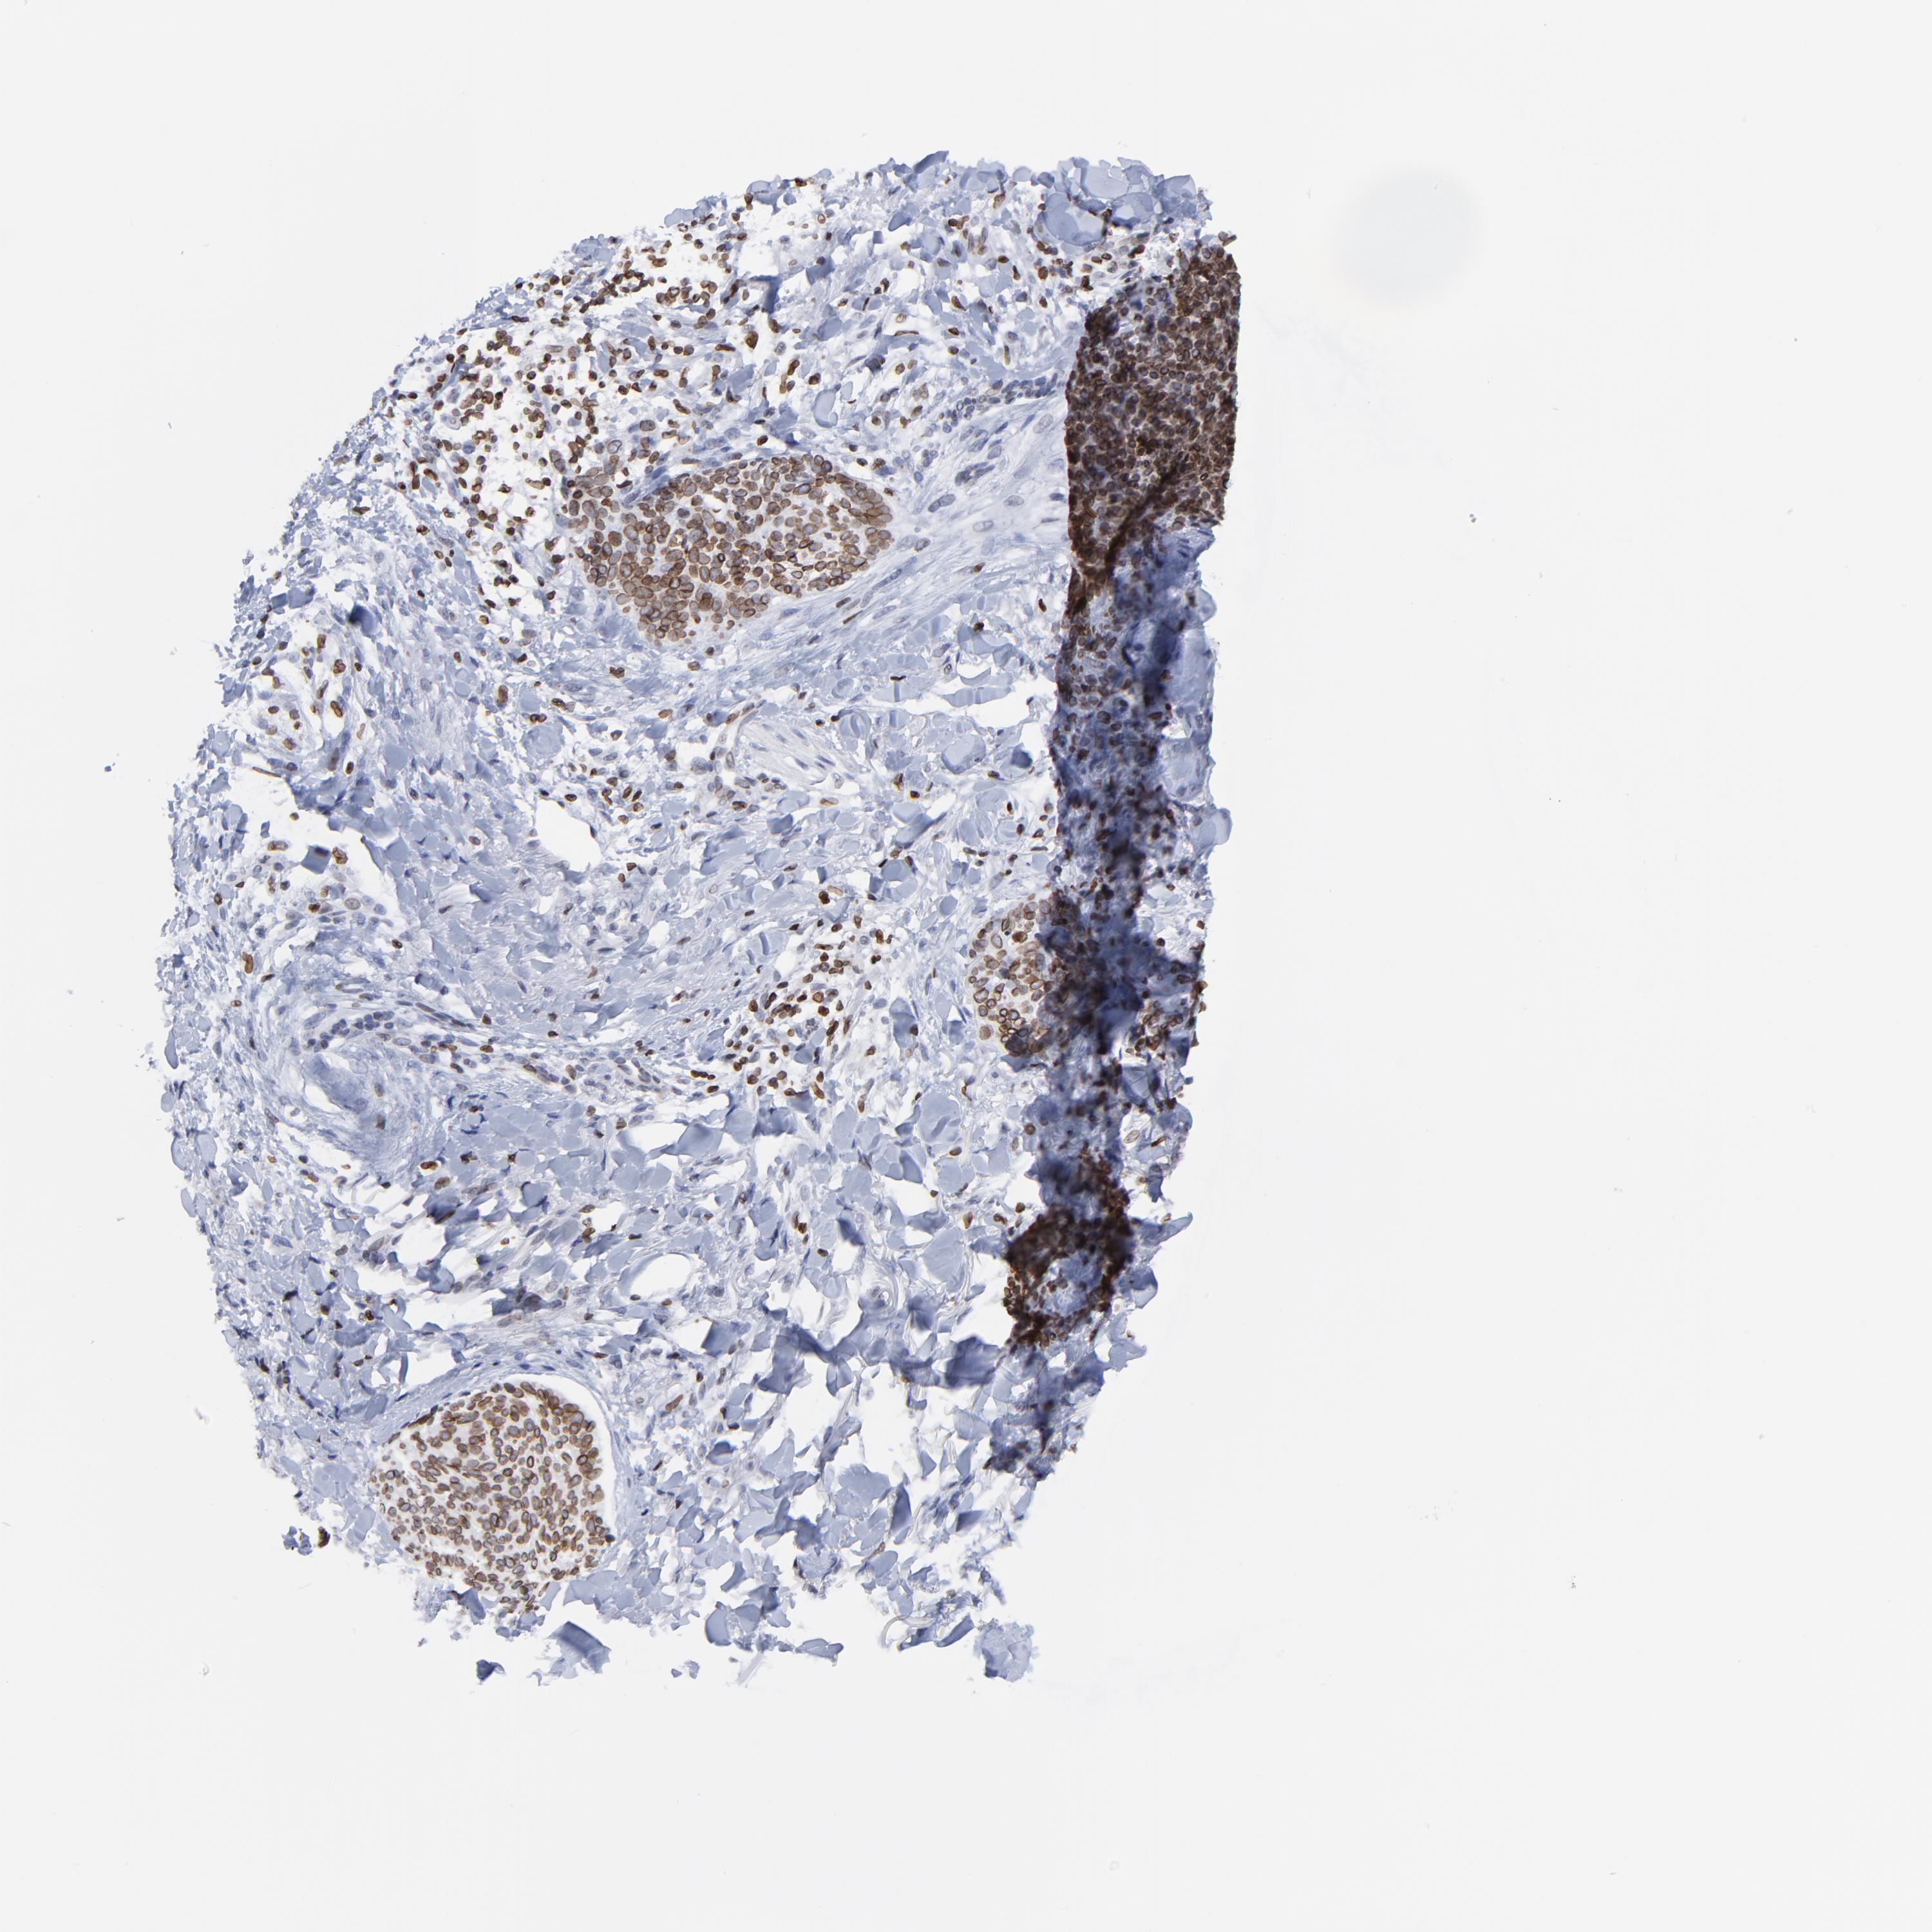

SKIN CANCER - Protein expressioni

A mouse-over function shows sample information and annotation data. Click on an image to view it in a full screen mode. Samples can be filtered based on level of antibody staining by selecting one or several of the following categories: high, medium, low and not detected. The assay and annotation is described here.

Antibody stainingi

Antibody staining in the annotated cell types in the current human tissue is reported as not detected, low, medium, or high, based on conventional immunohistochemistry profiling in selected tissues. This score is based on the combination of the staining intensity and fraction of stained cells.

Each image is clickable and will lead to virtual microscopy that enables deeper exploration of all samples and also displays staining intensity scores, fraction scores and subcellular localization as well as patient and tissue information for each sample.

Antibody HPA003083

Staining

High

Intensity

Strong

Moderate

Quantity

>75%

Location

Nuclear

Squamous cell carcinoma, NOS

Basal cell carcinoma